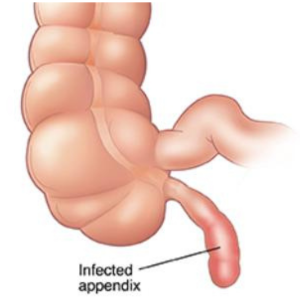

Surgeries We Offer

Appendicitis